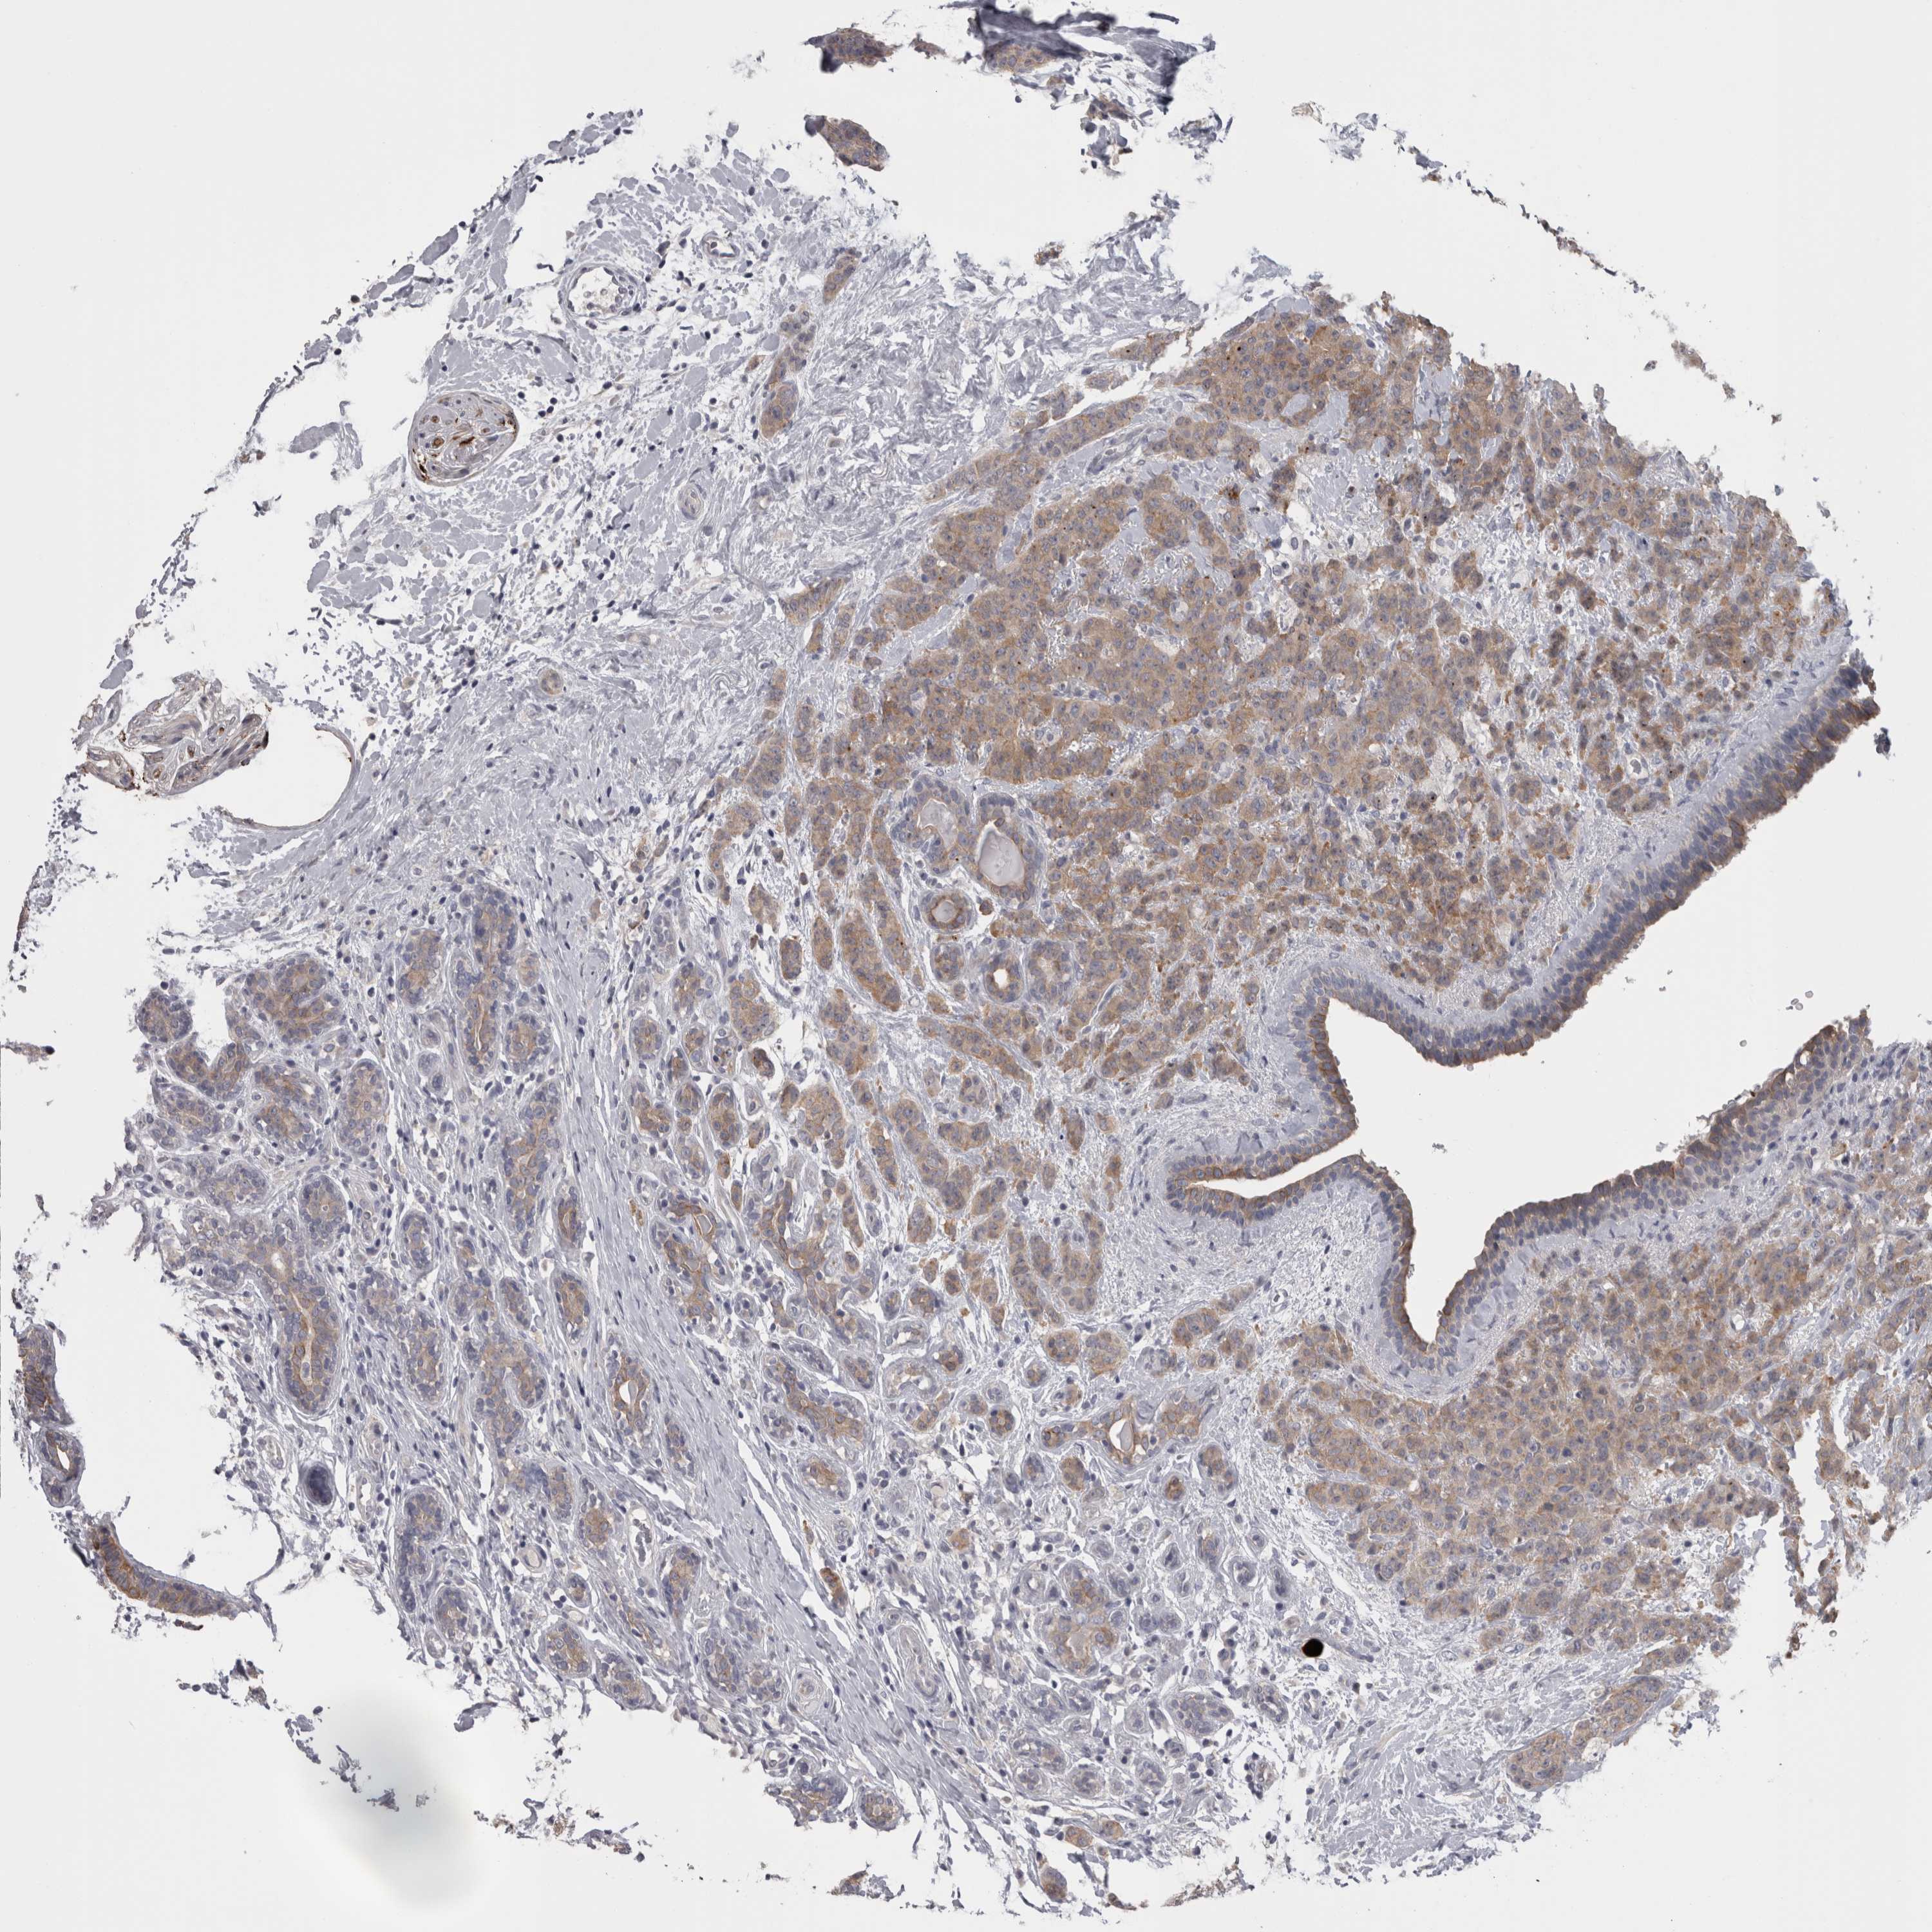

CANCER BREAST CANCER Show tissue menu

BRCA TCGA BRCA VALIDATION PROTEIN EXPRESSION